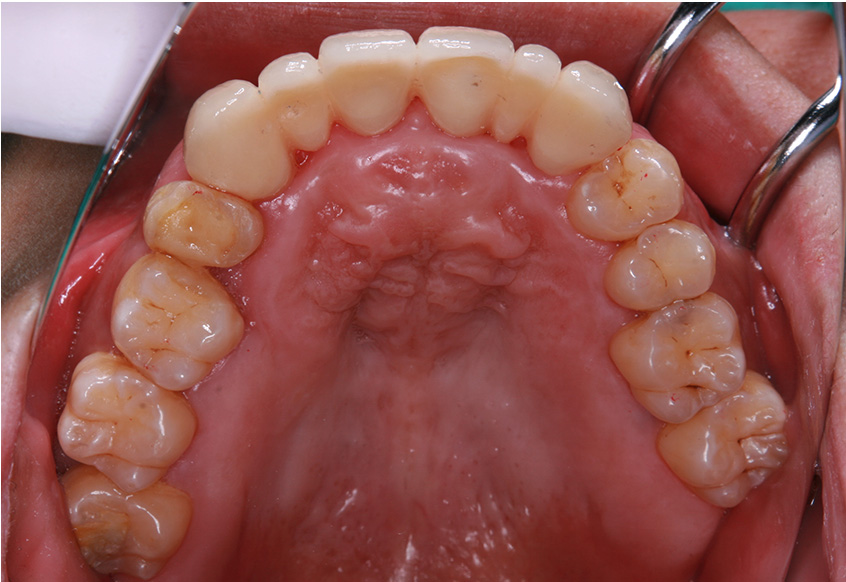

治療開始後3ヵ月経過すると、前歯の隙間や全体の乱れが減ってきました。口笛が吹けるようになったとのことです。

最初のお口の中 治療開始3ヵ月後

6ヵ月経過すると、矯正治療を終了し、前歯に被せ物の治療を行いました。

最初のお口の中 2025/3/22

| 治療内容 | 上顎側切歯を2本抜歯した後、上顎の歯にブラケットを装着し、ワイヤー、矯正用ゴムで歯の移動を行いました。その後、被せ物の治療を行って治療を終了しています。 |